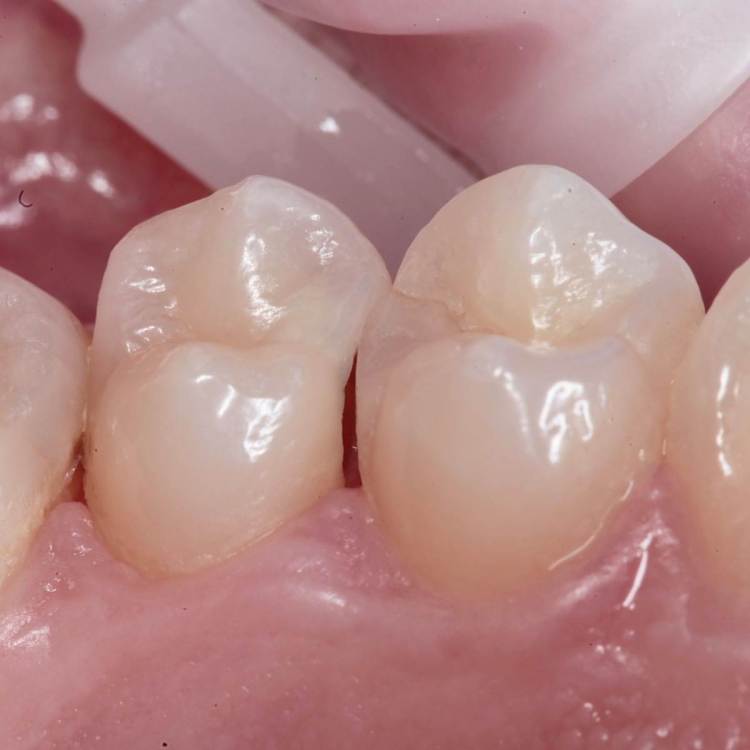

Эндо 25.06, 40.04, 60.02. Обтурация инжекторной техникой. Восстановление гармонайз а3 и желтая текучка от эстелайта (говорят ее сняли с производства, жаль, очень классный материал был)